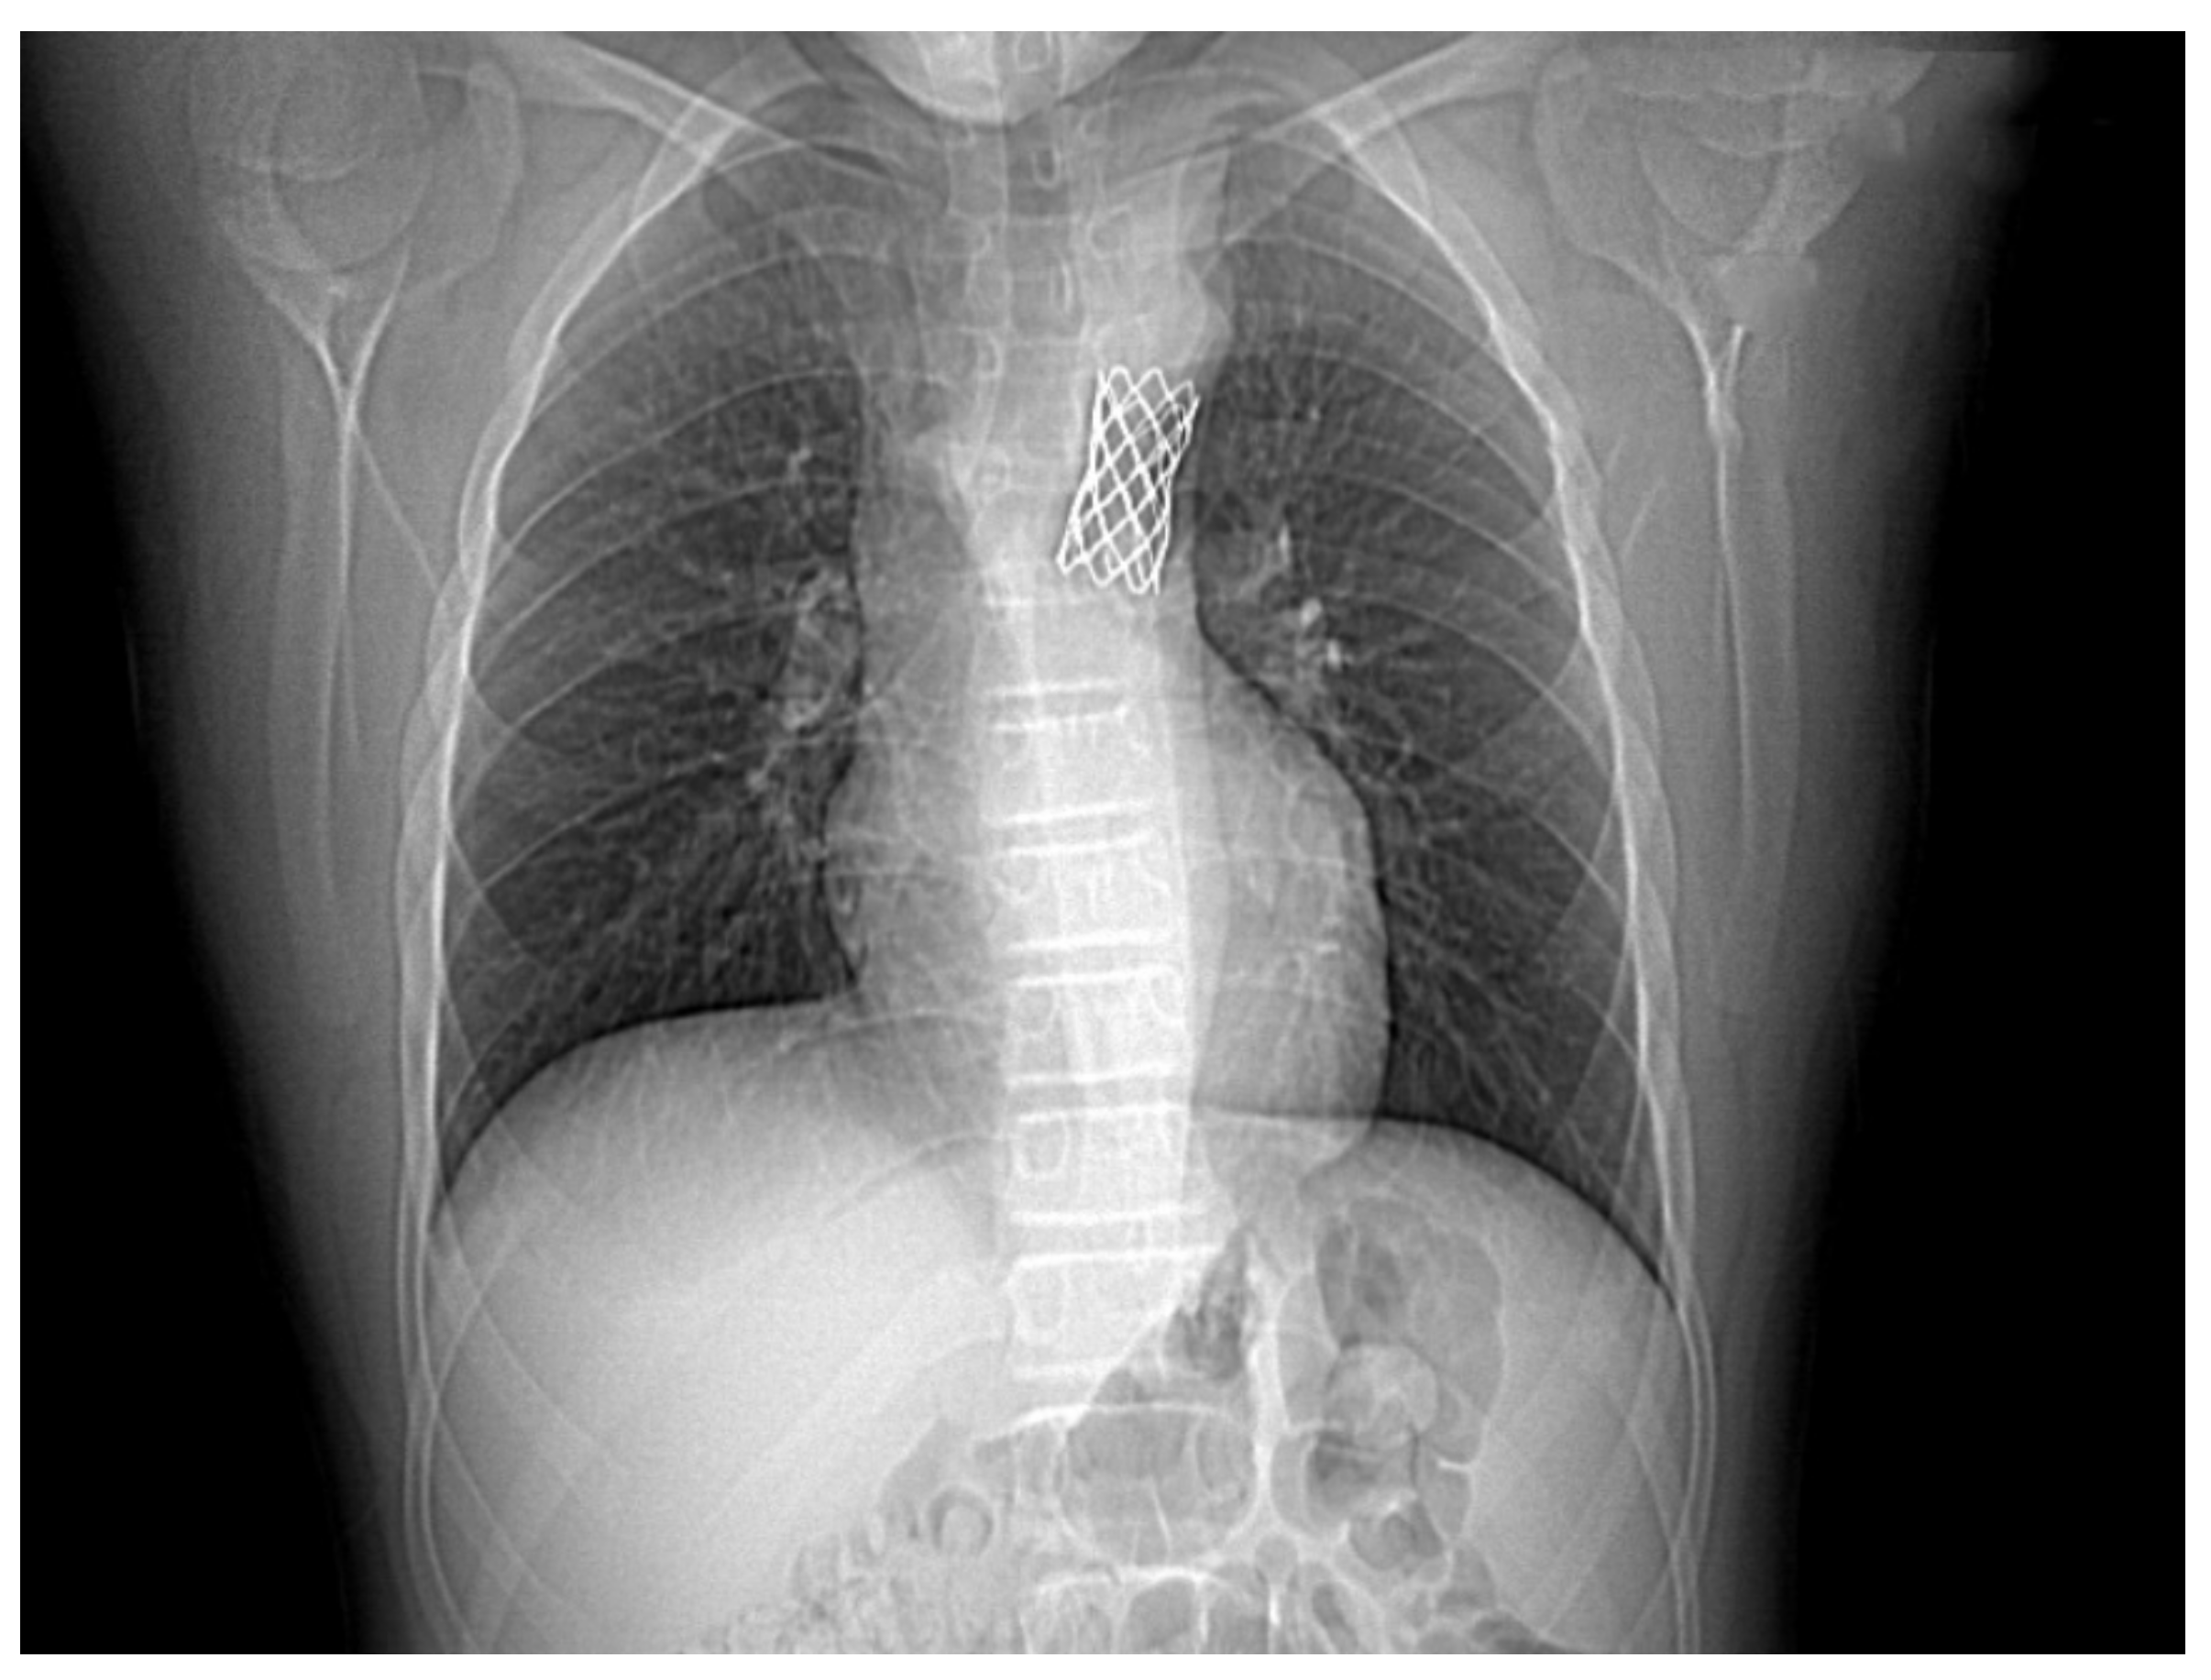

2.3. Therapeutic Approach, Postprocedural Evolution, Cardiologic Follow Up